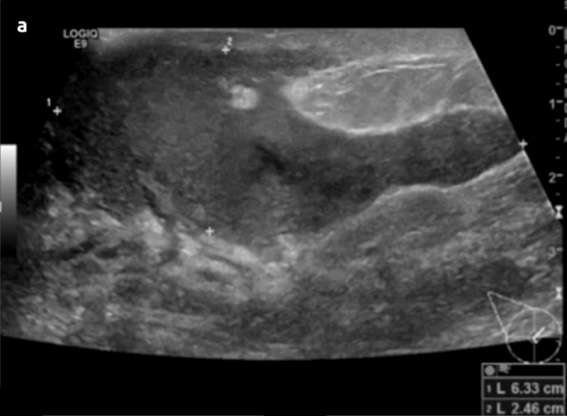

The most common complication includes breast abscess, occurring in 0.4-11% of patients with mastitis and is more frequently seen in cases of inadequately treated or late-presenting mastitis. If rupture of an abscess occurs, a resultant draining sinus and mammary fistula can occur. Diagnosis of lactational mastitis is based on clinical grounds, however ultrasound can be useful in differentiating between mastitis (ill-defined hypoechoic region) and a breast abscess (hypoechoic to anechoic mass with internal debris and surrounding vascularity) if there is a poor clinical response to antibiotics. Mammography is not usually performed but can show skin and trabecular thickening from breast edema.